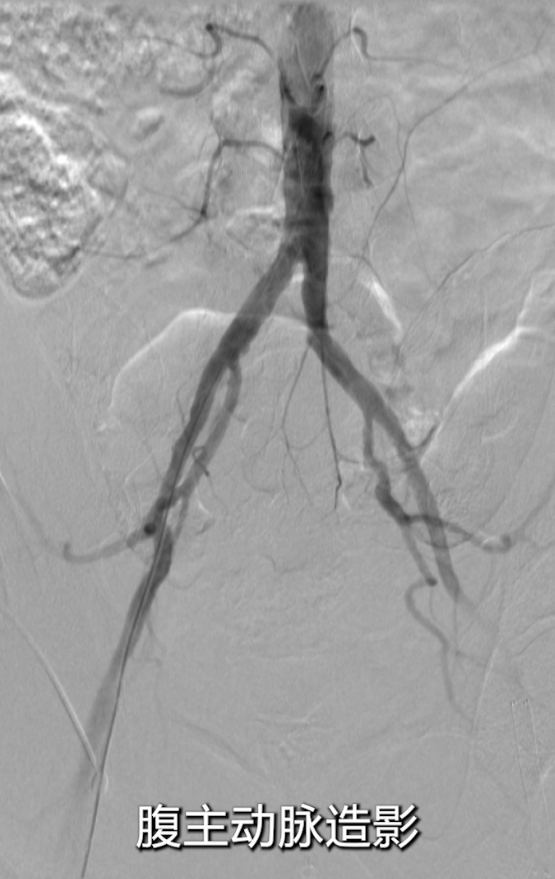

采用右侧股动脉入路,穿刺股总动脉后行基线造影;

腹主动脉及左侧股动脉造影显示:左侧股总动脉支架几乎完全闭塞,

支架长度较长(从股总动脉延伸至收肌管临近P1段),且部分遮挡股深动脉开口;膝下动脉显影稀疏,流出道条件差。